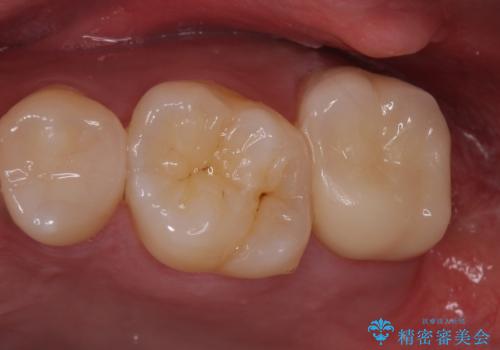

歯ぐきの形を整え、外れにくい被せ物を装着

- 銀の詰め物のやり替えを主訴に来院されました。

歯の奥が歯ぐきに埋もれている状態であったため、埋まっている親知らずを抜歯しつつ歯茎の高さを落とし、外れにくいジルコニアクラウンを装着していきます。

歯のみでなく歯茎の調整も行うことで、外れにくい被せ物を装着することが可能になります。